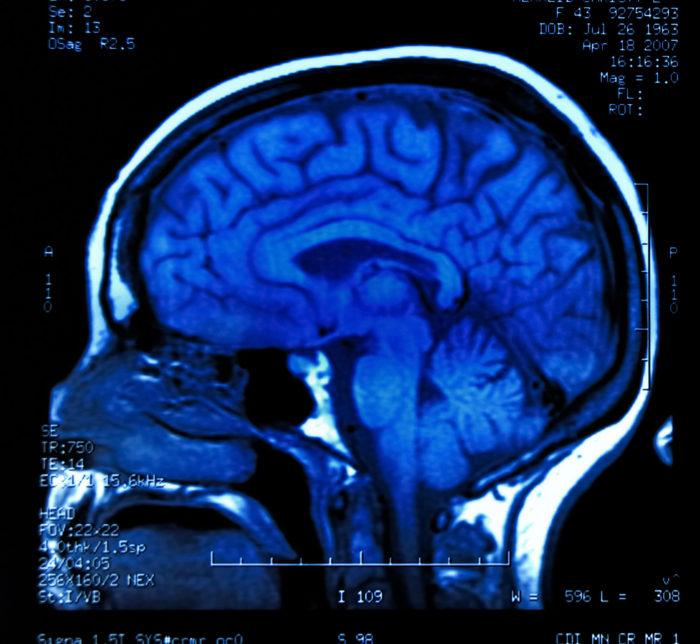

Dilantin side effects include cerebellar atrophy.¿Sufría usted o un pariente suyo de atrofia cerebelosa o degeneración cerebelosa mientras tomando la medicación Dilantin?

La atrofia cerebelosa (la atrofia del cerebro) ocurre cuando el tejido cerebral degenera y pierde neuronas y las conexiones entre sí.

La atrofia cerebelosa puede ser generalizada, que quiere decir que el cerebro entero ha encogido; o puede ser focal, afectando solamente a un área particular del cerebro y disminuyendo a las funciones que ese área controla. [Fuente: BrainFacts.org]

La atrofia cerebelosa es una atrofia cerebelosa focal, marcada por una degeneración del cerebelo, que es una parte del cerebro detrás del tronco encefálico. También se llama la degeneración cerebelosa.

El cerebelo se divide en dos hemisferios. El cerebelo ayuda con la regulación de movimientos voluntarios como la postura, el equilibrio, la coordinación, y el habla. El cerebelo permite el movimiento suave, equilibrado, y preciso.